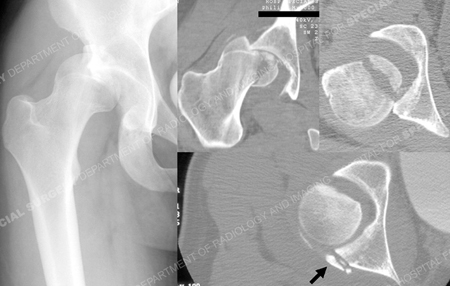

A previously healthy 18-year-old male was involved in a motor vehicle accident as a belted driver whose automobile struck a pole and was taken to a local hospital where evaluation revealed an isolated Pipkin IV Type posterosuperior fracture-dislocation of the right hip. Closed reduction was performed within two hours of the accident. A post-reduction CT revealed a congruent, located hip joint and reduced femoral head fracture. A small, peripheral posterior wall fracture of the acetabulum was identified. The patient was transferred to another hospital where he was admitted for observation. Four days later, he was discharged home, non-weight bearing with crutches. He presented to the HSS Orthopedic Trauma Service 20 days following the injury for definitive management by Dr. David L. Helfet with recurrent fracture dislocation of the hip and increased pain with passive and active motion. Vascular and neurologic examination was normal except for grade 3/5 motor strength in the foot plantar flexors. CT and MRI studies were performed to for further assessment. Comminuted fragments of bone were seen within and behind the joint, involving the posterior wall of the acetabulum and femoral head. A large medial fragment of the femoral head was found to be completely displaced from the remaining, lateral head. The middle third of the femoral head appeared to have a significant impaction injury.

Anteroposterior x-ray of right hip on presentation to the hospital after motor vehicle accident and (right image) CT scan showing coronal and axial images of femoral head and posterior wall of the acetabulum after hip re-dislocated (posterior wall fracture indicated with black arrow).